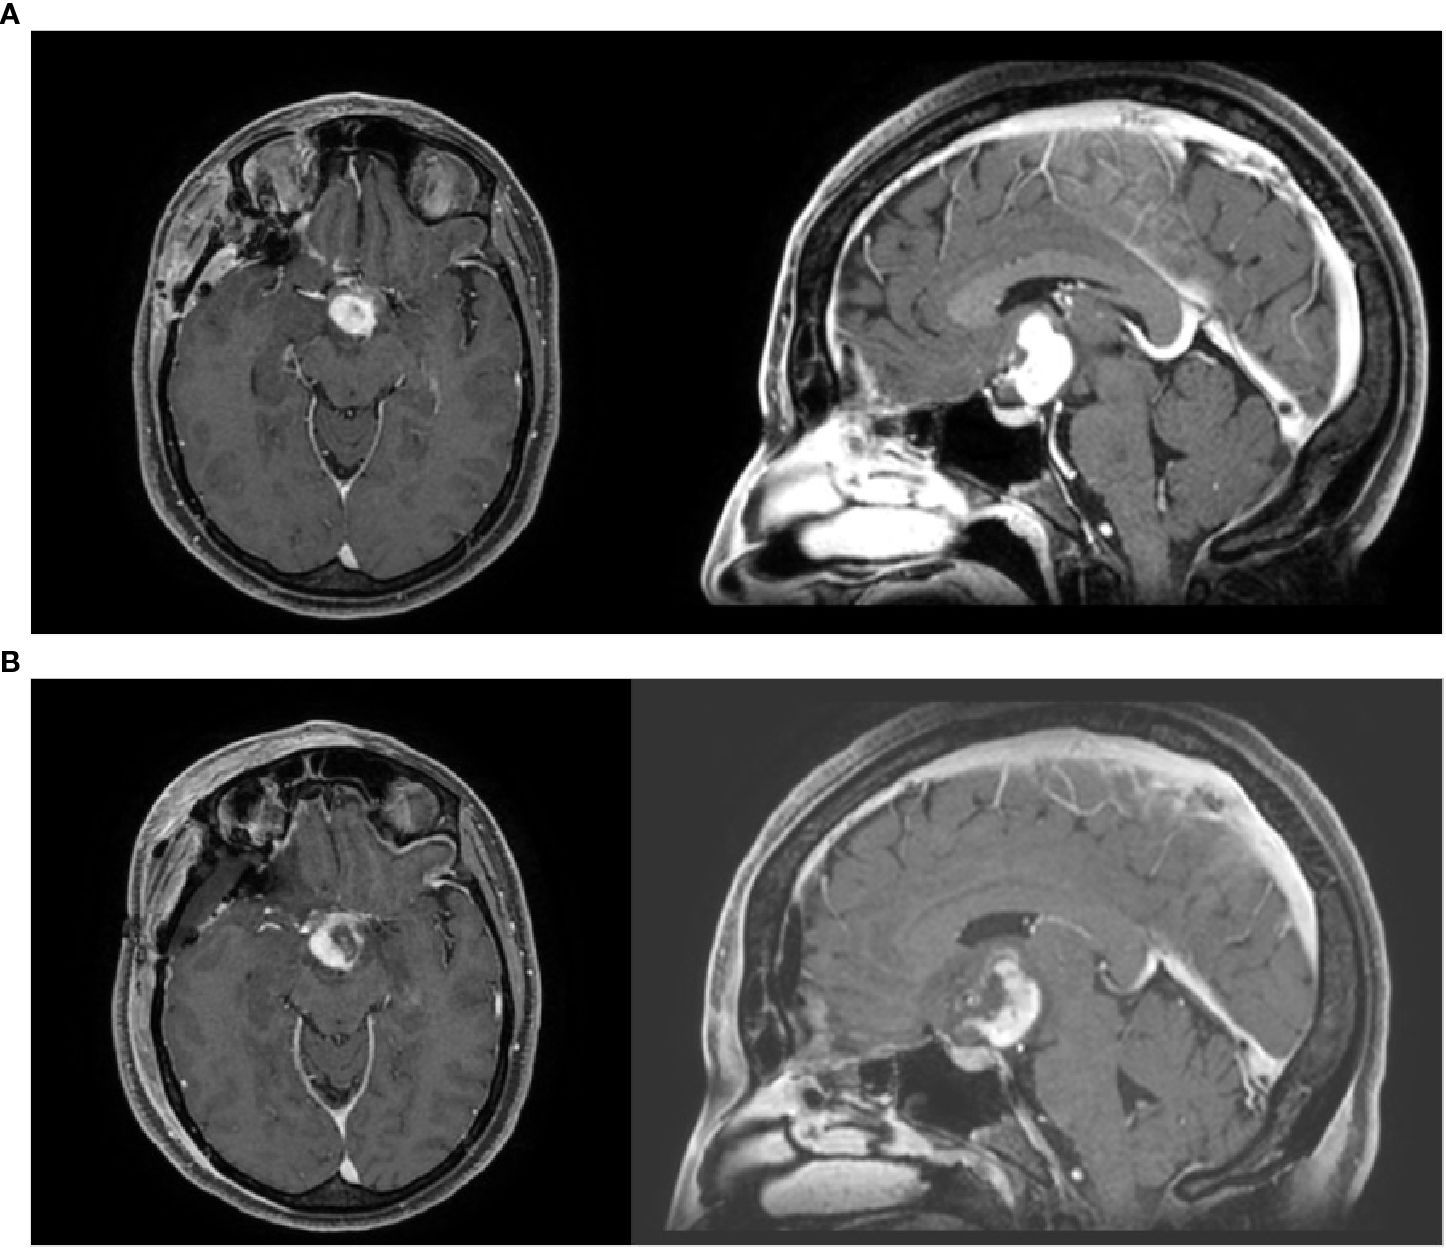

Background Chordoid glioma is a rare Grade II WHO brain tumor located in proximity of the third ventricle. Less than 100 cases are reported in the literature and surgery represents the main treatment option. Due to the typical location, complete surgical resection is uncommon, but the role of adjuvant radiotherapy is controversial. Methods Starting from a case report, we performed a literature review focused on the potential role of adjuvant radiotherapy for chordoid gliomas, reporting data on patients'characteristics, surgical approach and extent resection, radiotherapy technique and dose, and clinical outcomes. Results A total of 18 patients in 14 studies were identified, with a prevalent use of stereotactic treatments over conventional external beam radiotherapy, with doses respectively ranging between 11.5-18 Gy and 45-59.4 Gy, for a median time of local control of 26 months. Five patients developed disease recurrence after a median time of 22.4 months. In the case of the present study, the patient received adjuvant conventional radiotherapy (59.4 Gy/33 fx) is alive after 12 months of follow-up with no major side effects Conclusions From the available evidence, modern radiotherapy could be considered as a therapeutic tool able to conjugate less invasive surgical procedures with improved local control, thus reducing the risk of severe post-operative complications. Larger studies with longer follow-up are mandatory.